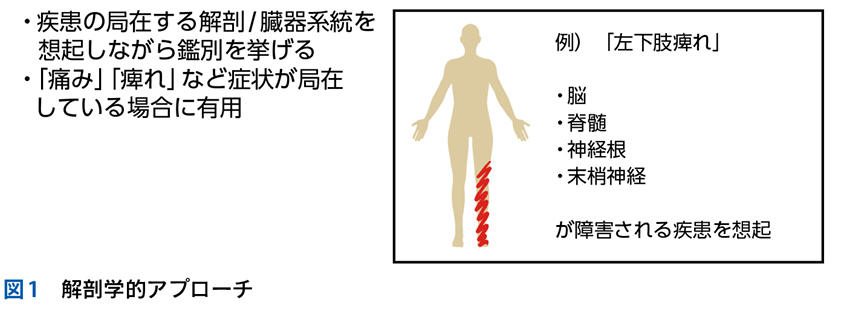

▶ 筆者の提唱する,分析的診断の「型」を図1に示した。冒頭に述べた「オリオン座を分析的に同定する手順」になぞらえ,診断推論を5つのステップにわけている。1つずつ解説しよう。

▶ また,ダイレクトに疾患の診断が行いにくい場合にはいったん「症候群名」で鑑別を挙げ,症候群診断を行い,診断された症候群を新たなフレームとしてその原因疾患の鑑別に移るという方法をとる。本章の最初に掲げた図1のステップ④で「症候群診断なら①に代入」とあるのはこのことである。